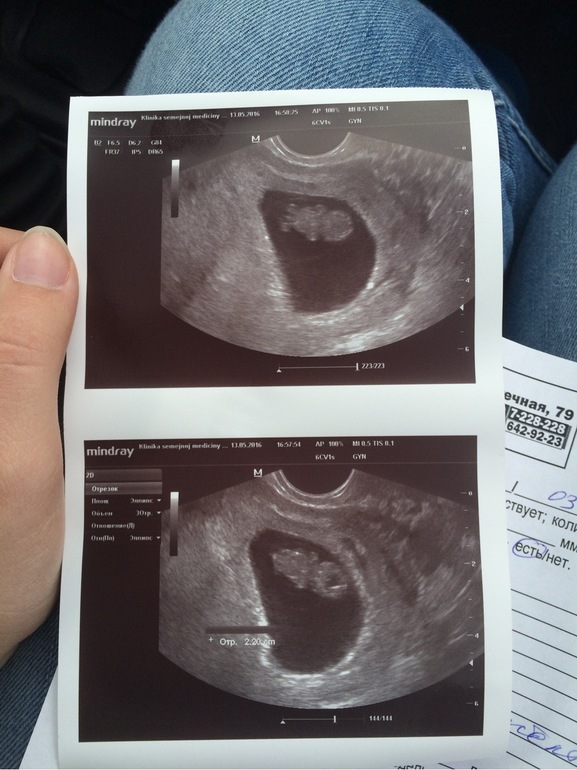

9 Акушерская Неделя Фото